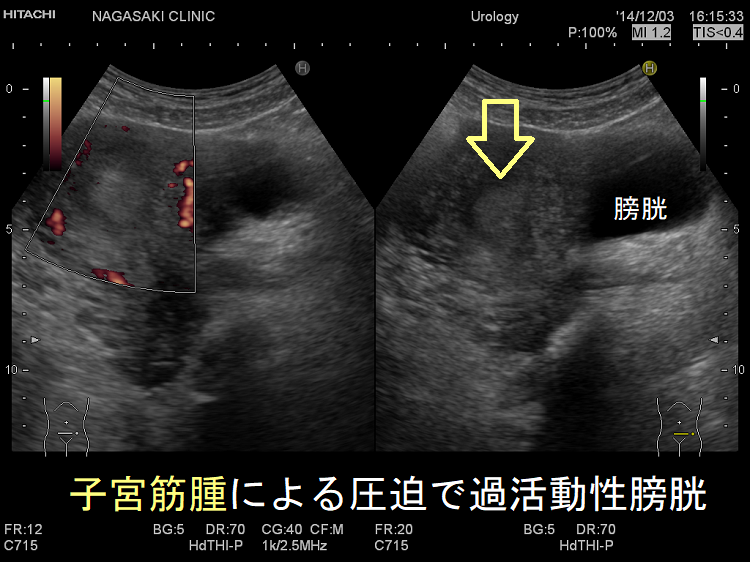

過活動膀胱の原因として、

- 加齢・精神的ストレス

- 膀胱内にある尿量センサーが過敏になる(間質性膀胱炎)

- 脳の排尿中枢の異常(脳梗塞後)

- 排尿に関与する自律神経障害;パーキンソン病(Parkinson 病)では下部尿路症状を30~40%に認める。脊髄損傷

などがあります。

脳が関与しているためか、トイレのことを考えただけで尿意出現。トイレに向かう間に尿意は猛烈に強くなります。